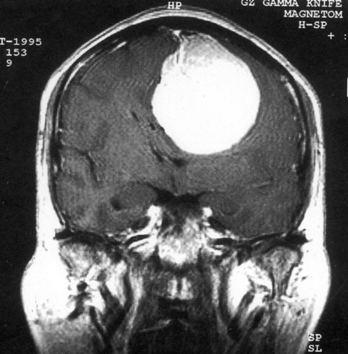

问题 病历摘要:??患者女性,37岁。大便时突起炸裂样头痛3小时,伴喷射样呕吐。既往体健。体检:T37.5℃,BP145/90mmHg,R20次/分,P85次/分。神志清楚,颅神经检查无异常,颈强直,克、布氏征(-),四肢肌力、肌张力正常,病理征(-)。 按Hunt&?Hess的动脉瘤危险性分级,该患者可分为几级?